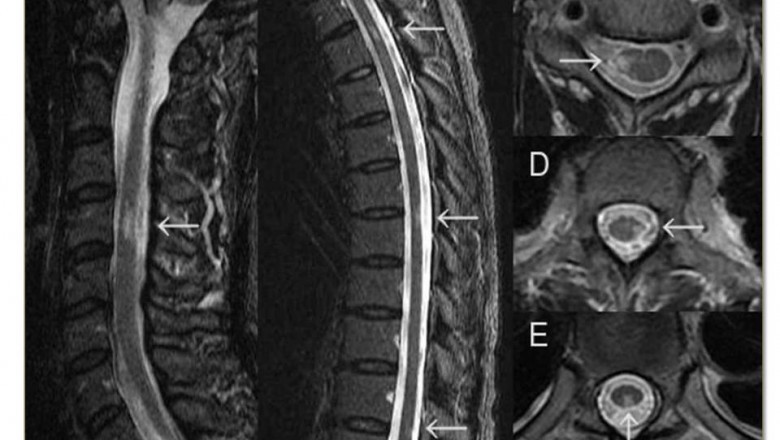

- Radiological examination-

- CT scan (Computed tomography scan)

- MRI scan (Magnetic resonance imaging)